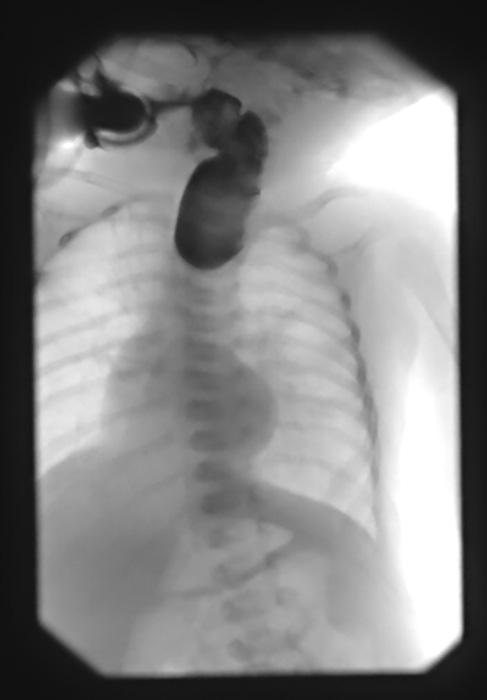

What may be seen on chest X-ray for achalasia?

Widened mediastinum with an air-fluid level.